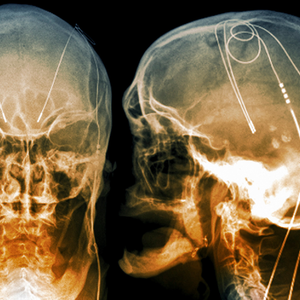

DBS is an incredibly promising intervention for intractable neurological and psychiatric illness. What are the risks?